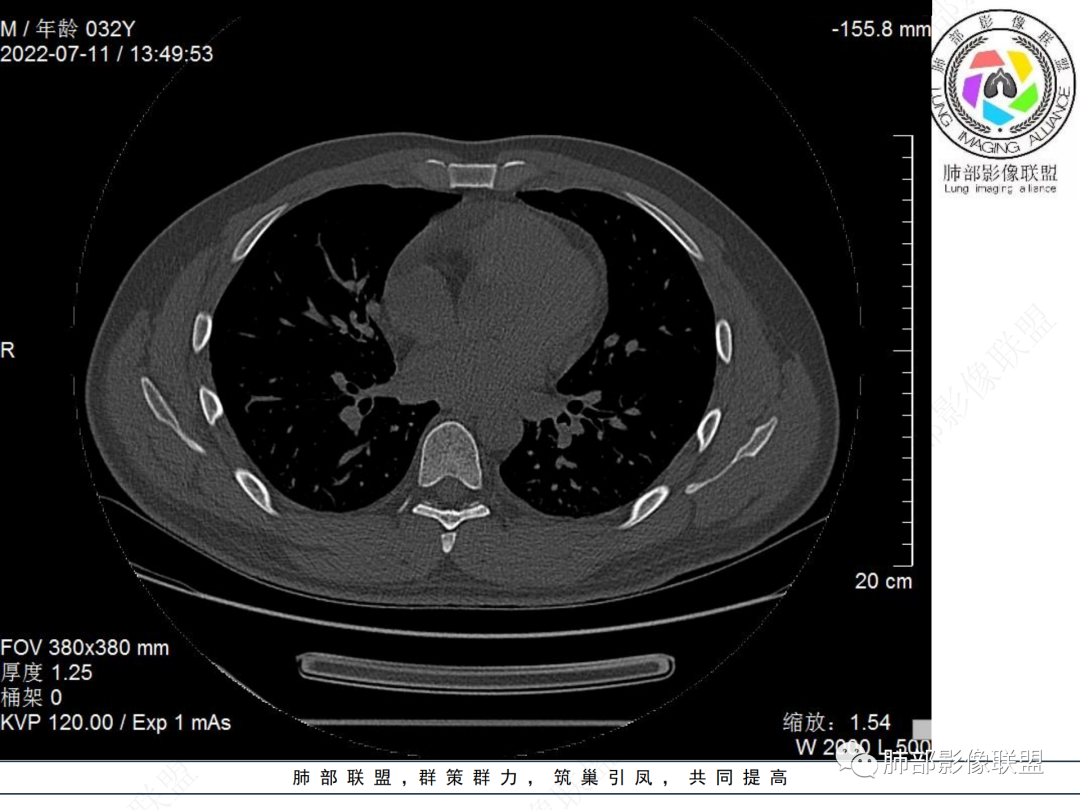

左肺下叶后基底段开口处结节,边缘光滑清楚,没有增强扫描,年轻男性患者痰血三天,考虑1.良性病变:腺瘤、错构瘤、平滑肌瘤

2.恶性:类癌、粘液表皮样癌。

左肺下叶外后基底段气管内见结节状影,边缘部分清晰。考虑错构瘤,待排恶性病变。

左肺下叶气管内外占位病变,咯血病史,考虑类癌,粘表待排。

青年男性,左肺下叶后基底段支气管开口软组织结节,边缘光整,气管镜提示质软,易出血,考虑类癌

IMT常表现为边缘清晰的周围型结节或肿块,一般体积相对较大。大约10%-20%发生于支气管及气管腔内,表现为中央型病变,一般为单发。IMT胸部CT显示90%为单发结节或肿块。

IMT的影像表现缺乏特异性。部分肿块表现为桃尖征和边缘平直征,界限可清晰有分叶状轮廓,也可界限模糊具有粗长毛刺。肺IMT的CT表现特征与病理具有相关性,可伴有囊变、局灶性钙化、肺实变和空洞样表现。CT增强扫描呈多样性,强化形态和CT值增加幅度呈多样性。粘液血管型增强CT实性成分呈明显花环样强化,静脉期强化进一步增高,此与毛细血管增生与血管管壁通透性增加有关。囊性低密度无强化区镜下为黏液样变形、炎性渗出或坏死。梭形细胞密集型增强扫描呈渐进性延迟强化特点,但强化程度弱于黏液血管型。少细胞纤维型增强扫描实性成分强化不明显或呈轻中度强化。PET/CT上IMT具有很高的SUV值。IMT高摄取的可能原因可能与激烈炎症导致的代谢活动增加有关,这使得IMT与其他恶性肿瘤难以区分。